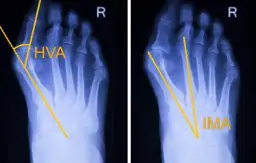

Zrozumienie, jak haluksy zmieniają stopę, jest kluczowe. Deformacja ta ma swoje stadia zaawansowania, od wczesnych, niemal niezauważalnych zmian, po zaawansowane, gdzie paluch może nachodzić na inne palce. Lekarze oceniają stopień koślawości palucha na podstawie specjalnych kątów mierzonych na zdjęciach rentgenowskich, co pozwala na precyzyjne określenie zaawansowania problemu.

Profesjonalna diagnoza haluksów u ortopedy rozpoczyna się od dokładnego badania fizykalnego stopy. Specjalista oceni zakres ruchu, elastyczność deformacji oraz stopień bólu. Kluczowym elementem diagnostyki są jednak zdjęcia RTG stóp wykonywane w obciążeniu, czyli na stojąco. Dzięki nim lekarz może precyzyjnie ocenić kąty deformacji kości i zaplanować dalsze leczenie.